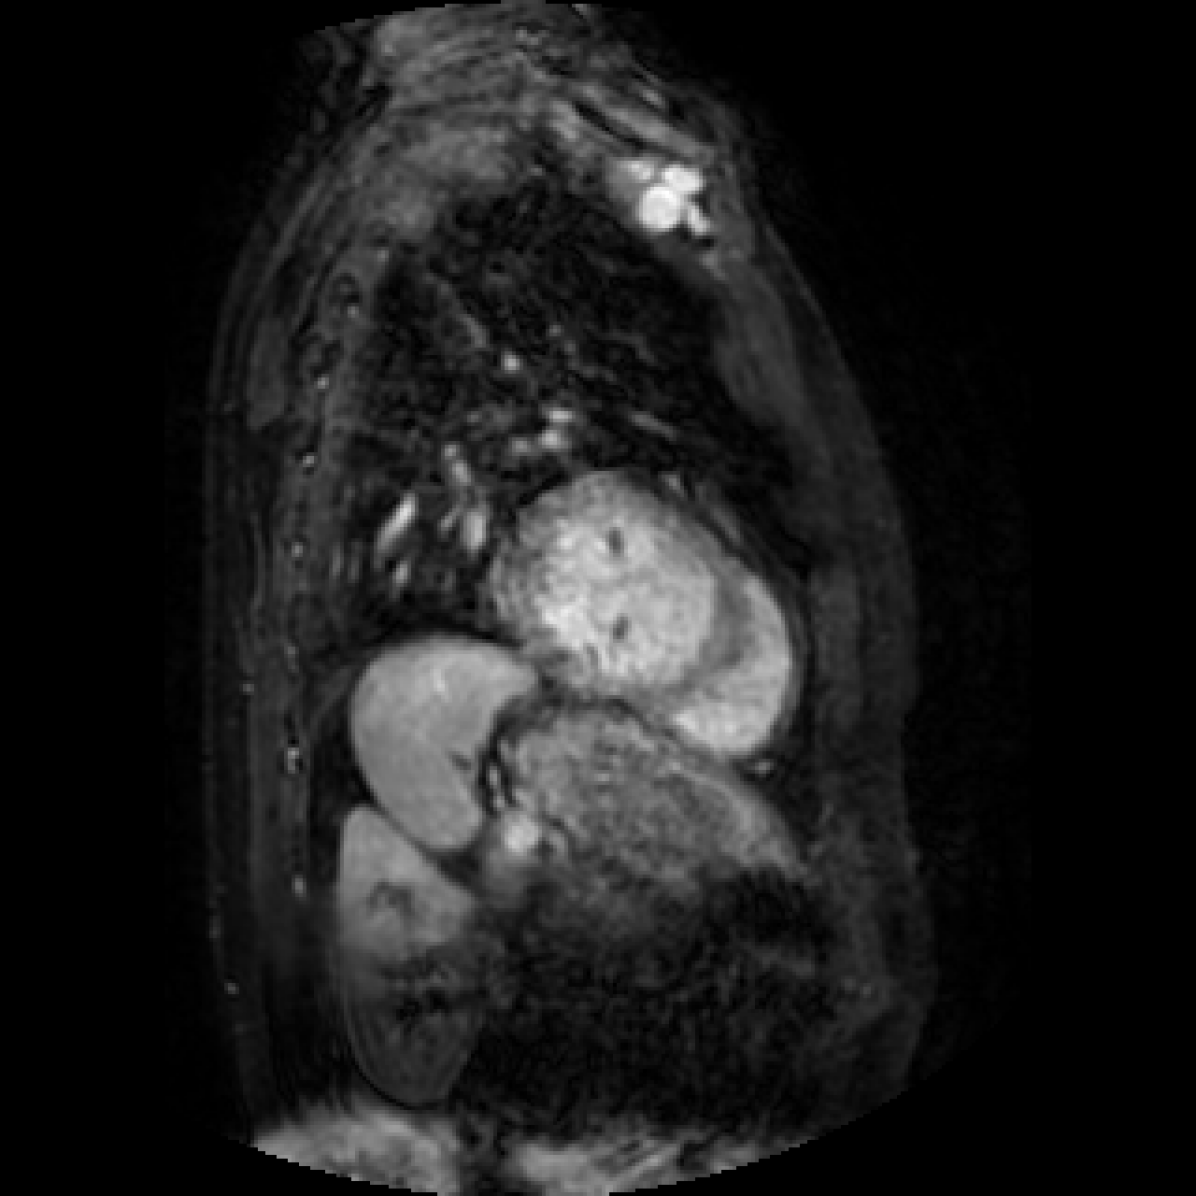

In this section we will show qualitative results of DINOv2 features using principal component analysis (PCA) performed on DINOv2 patch features on X-ray, CT, and MRI scans, following the method delineated in [8]. We will also provide organ segmentation results of linear compared U-Net decoders.

PCA visualization. Figure 2 shows the first three PCA components. The PCA is computed between patches of images that are in the same column, and the first 3 components are shown for X-ray, CT, and MRI scans. Thresholding is used on the first PCA component to remove the background. Just like in natural images [8], the colors of the three PCA components correspond well with the same parts of images in the same category. This is an easier task however, compared to natural images, because there is less variability between examinations on medical images compared to natural images.

U-Net and linear decoder visualization. We also show a visualization of linear and U-Net decoders trained on top of DINOv2 ViT-L/14 features. The linear layer decoder performs surprisingly well, but is limited, especially on smaller masks, due to the smaller decoding map (32x32 pixels interpolated to 448x448) and less adjustable parameters. As expected, the U-Net segmentation results are smoother and represents the ground truth mask more accurately, but is still limited due to the frozen encoder.